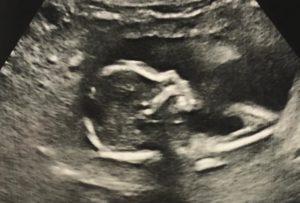

Here we have the latest ultrasound of the new baby. Not much to look at, but according to the person who was conducting the test, everything looks normal. Well, as normal as it can look at this stage. And I did ask; they couldn’t tell what the gender is so far. At this point whether it’s a boy or a girl doesn’t matter… as all mom and I want is a child that is healthy and happy.

Back to the subject at hand… and based on the ultrasound she just took, the due date has been estimated as January 13th, 2025. That is a little over 6 months from now, and trust me that time will fly. Kat’s mom also has a history of never making it to the due date… so I’m assuming she will hatch early again this time too. How early you ask? There is a very good chance that this could still be a December baby, so that early.